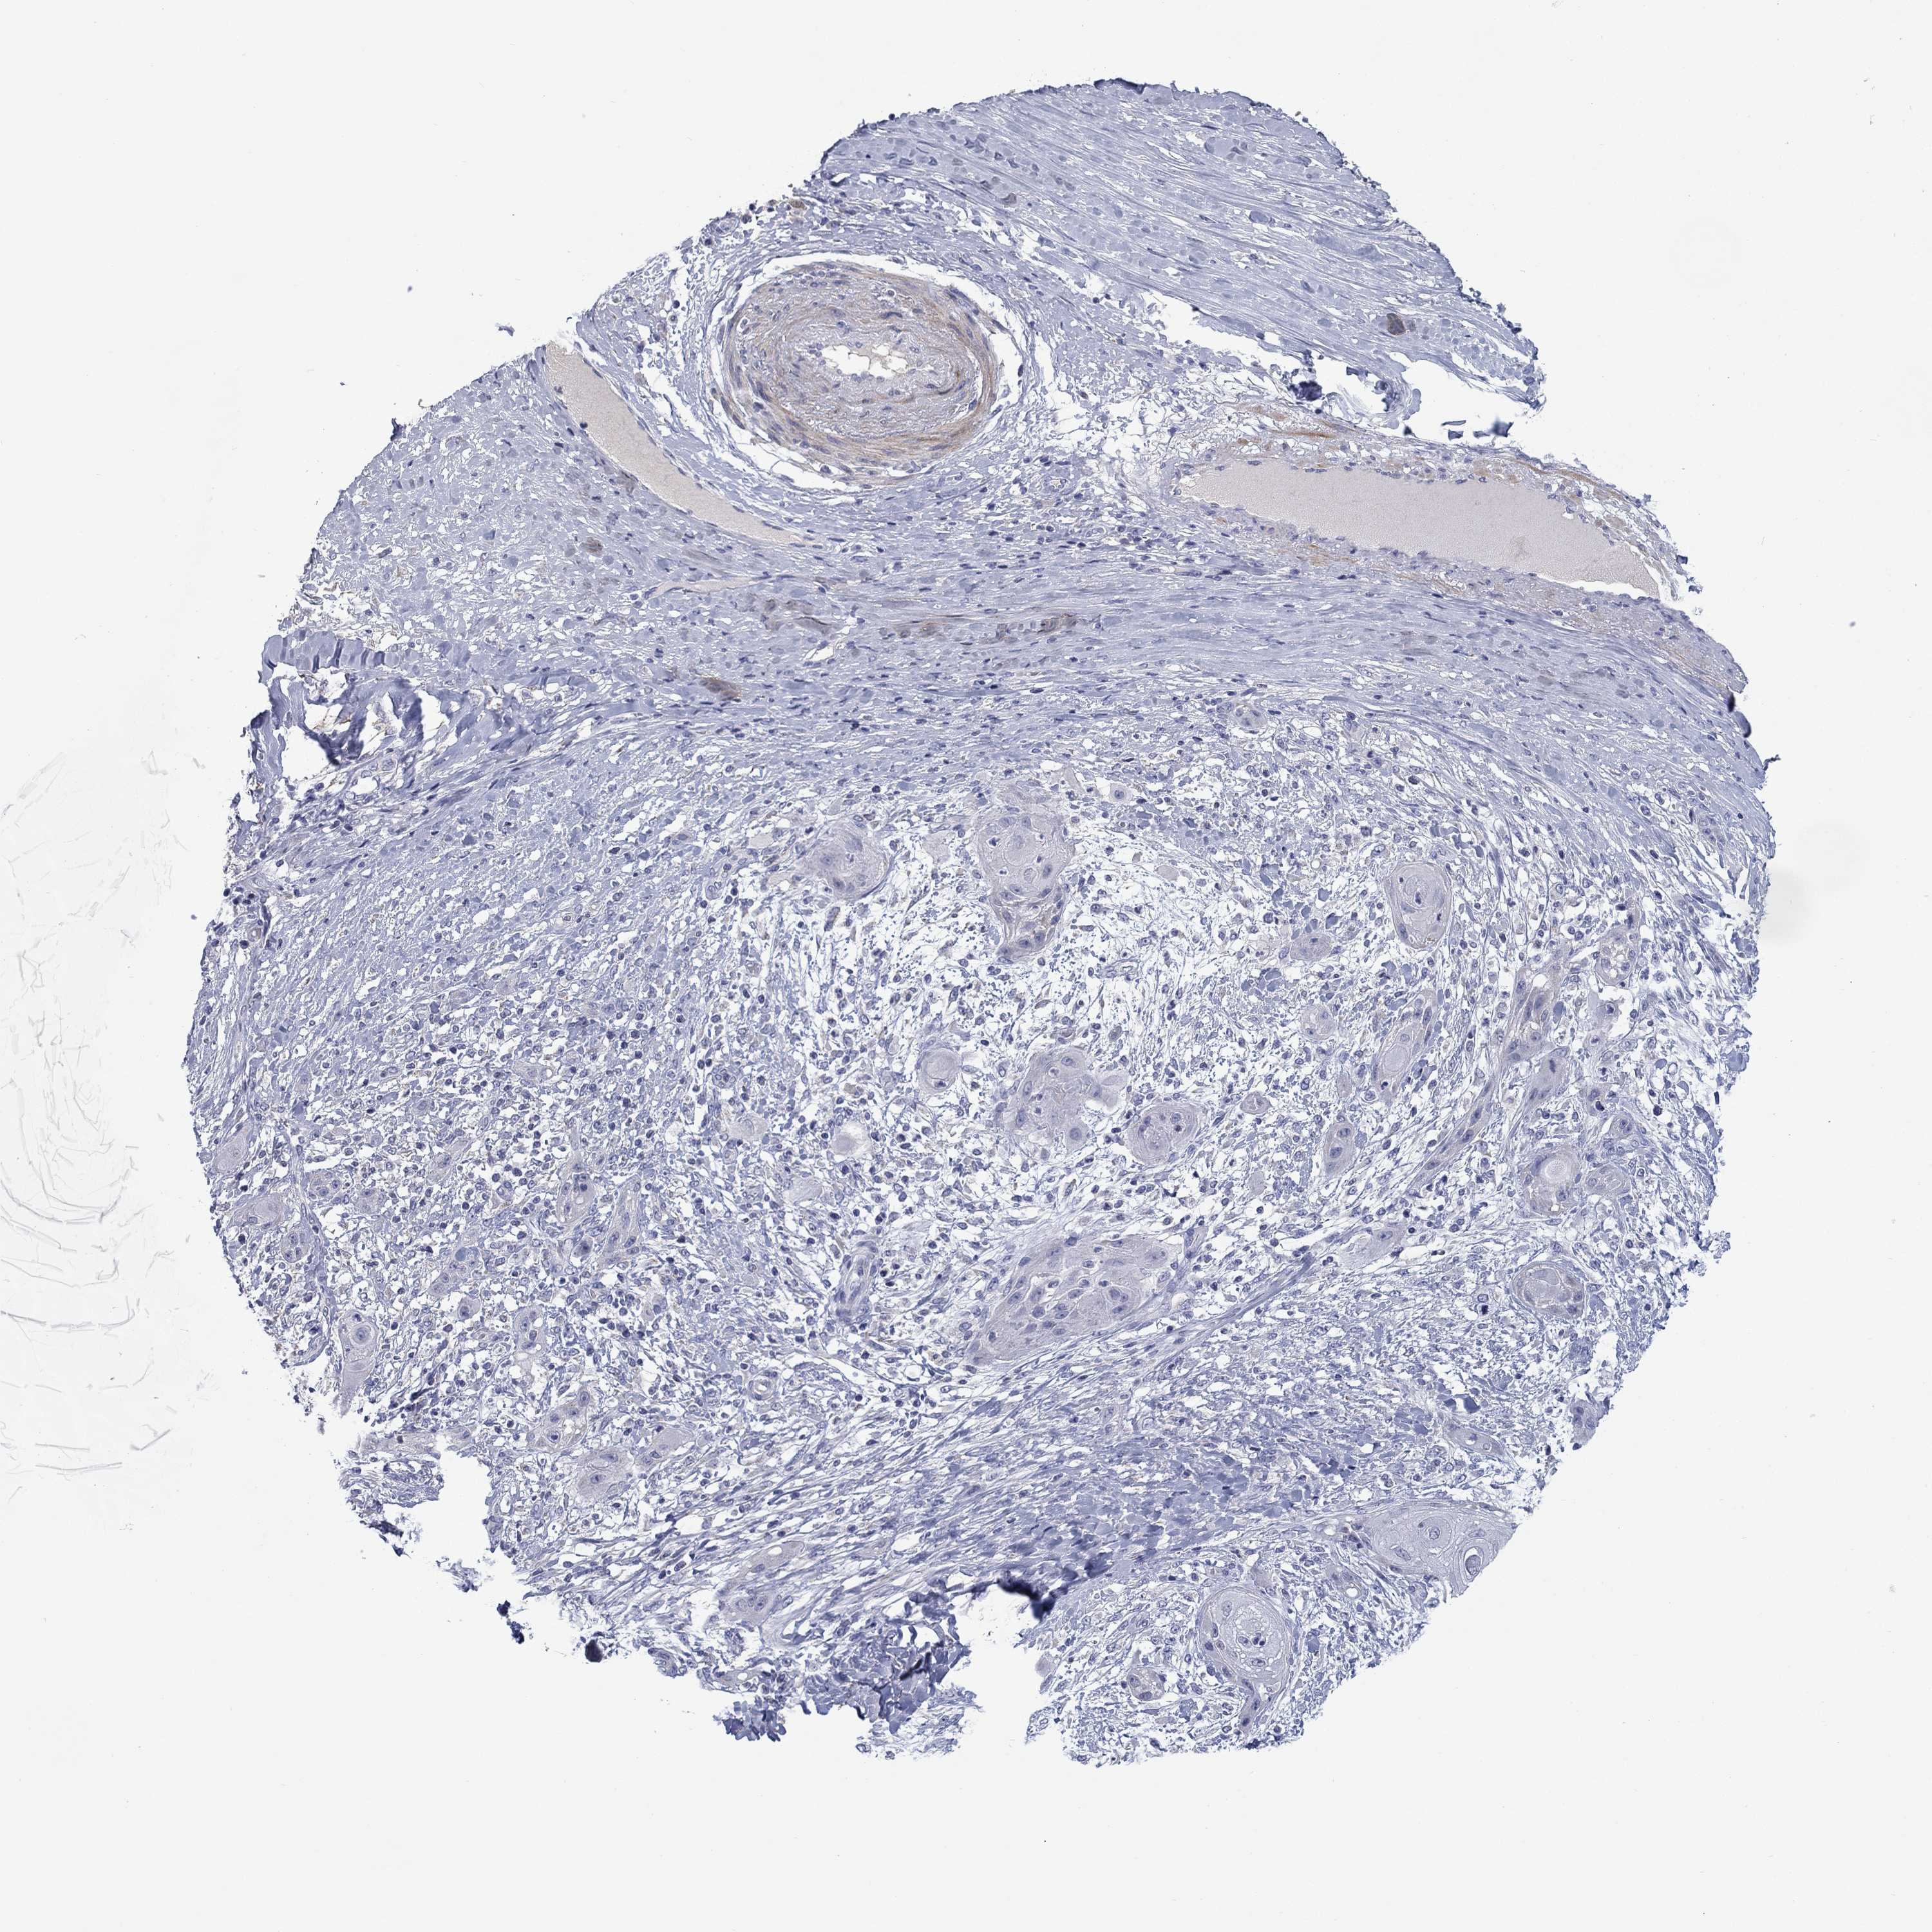

Basal cell and squamous cell cancer

SKIN CANCER - Protein expressioni

A mouse-over function shows sample information and annotation data. Click on an image to view it in a full screen mode. Samples can be filtered based on level of antibody staining by selecting one or several of the following categories: high, medium, low and not detected. The assay and annotation is described here.

Antibody stainingi

Antibody staining in the annotated cell types in the current human tissue is reported as not detected, low, medium, or high, based on conventional immunohistochemistry profiling in selected tissues. This score is based on the combination of the staining intensity and fraction of stained cells.

Each image is clickable and will lead to virtual microscopy that enables deeper exploration of all samples and also displays staining intensity scores, fraction scores and subcellular localization as well as patient and tissue information for each sample.

Antibody CAB025217

Staining

High

Medium

Low

Not detected

Intensity

Strong

Moderate

Weak

Negative

Quantity

>75%

75%-25%

<25%

None

Location

Nuclear

Cytoplasmic/membranous

Cytoplasmic/membranous,nuclear

Squamous cell carcinoma, NOS

Squamous cell carcinoma, metastatic, NOS